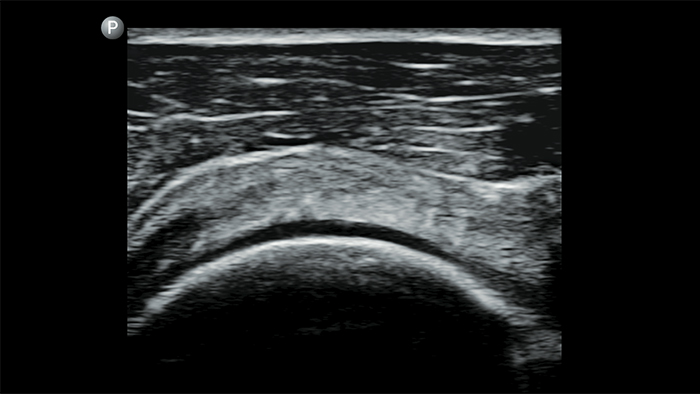

Lumify handheld ultrasound offers images that enhance diagnostic confidence.

See more when it counts

Lumify can help you make real-time decisions with more confidence, from assessment to recovery. Reveal the subtle details of an image, uncover enriched tissue definition with multiple angles and much more.